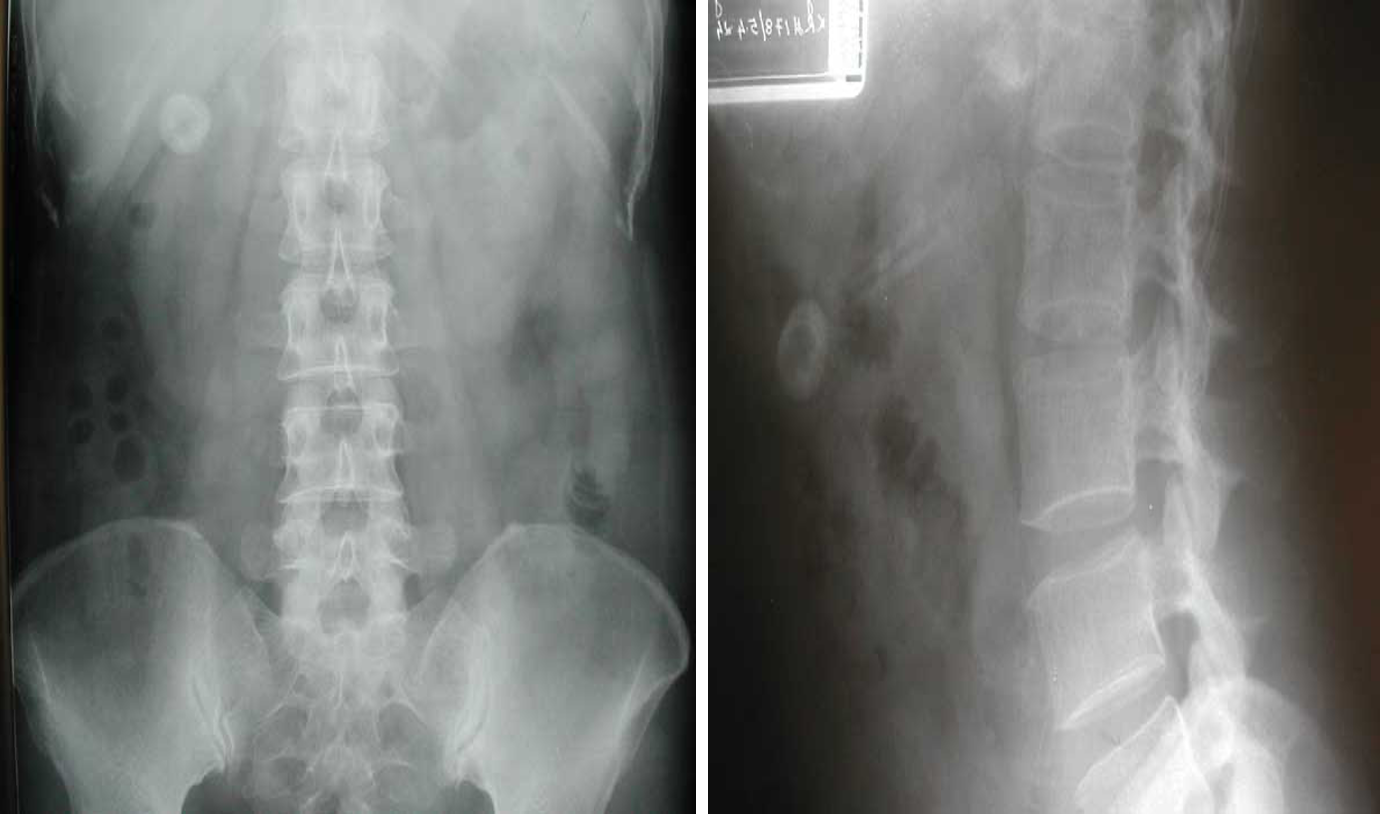

Abdomen Imaging

normal abdominal x-ray - normal gas pattern - lower pole kidney - gastric bubble is found - comment on bone

- Uretic stone

- radioopaque shadow on RUQ - renal stone